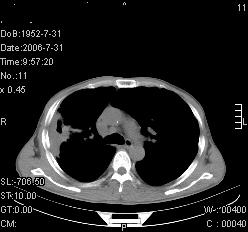

患者,男,54岁,咳嗦,咳痰20天。抗炎治疗2周。现esr76mm/h,目前患者症状明显好转,但发现两次ct片未见明显变化。两次分别做与7.25、7.31。第一次诊断右肺上叶炎症累计胸膜。大家看,从影像上内排除结核吗?

结核的可能性非常大,右上肺病变应该考虑干酪性肺炎。理由:

1.纵隔内多发淋巴结肿大。

2.esr76mm/h。

3.虽经抗炎治疗肺窗病灶有所吸收、减小,但纵隔窗病灶形态、密度、范围无明显变化。如果是单纯的大叶性肺炎,“抗炎治疗2周,目前患者症状明显好转”病灶应该基本消散了,至少也处于吸收消散期,密度变淡、范围变小。同时本病例所示其内的密度不均匀,见多发大小不一空洞样影也不符合大叶性肺炎吸收消散期表现。

病灶特点:片状 索条 结节混杂影,部分融合,密度不均,广泛累及相应胸膜.

临床治疗;二周未吸收.但症状好转.

多考虑:肺结核.